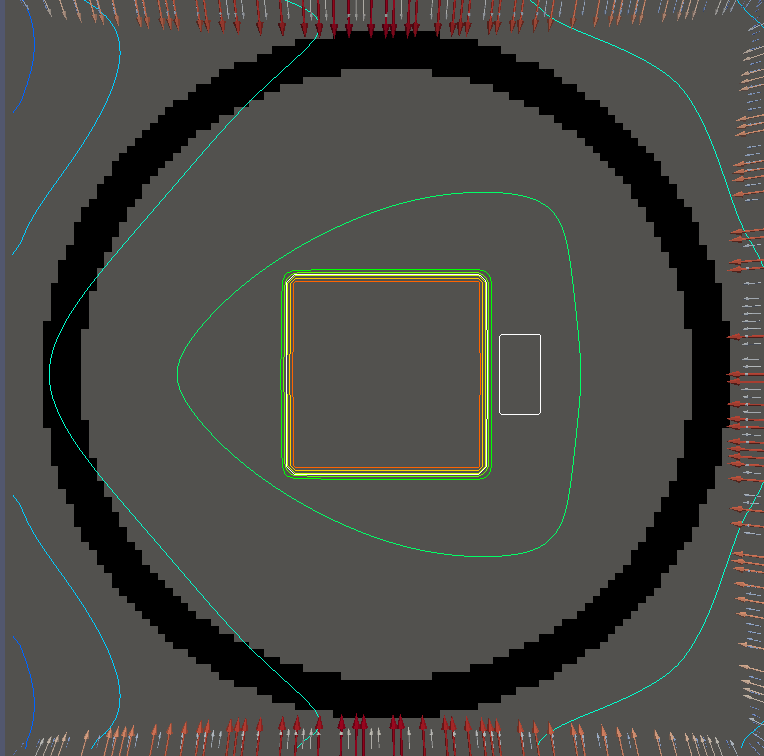

For testing, we use three tumor/risk region regions similar to those in [13]. Specifically, we define the regions in Table 3 and are shown in Figure 1; the void region is shown in black and the tumor and risk regions are traced in white. In the basic target case, seen in Figure 1(a), the tumor region is a box, as is the risk region. The second, intermediate target case, seen in Figure 1(b), involves an L-shaped tumor around a box-shaped risk region. Finally, the complex target case in Figure 1(c) involves a C-shaped tumor around a risk region.

We will solve both and for each geometry seen in Figure 1. For for each example, we set on and elsewhere, corresponding to an average (over time) dose of and

Figure 2 shows the optimal boundary source term for both and The vectors shown on the boundary are the time-integrated values of normalized and then scaled by In Figures 2(a), 2(c), and 2(e) (corresponding to ), the isolines are spaced at intervals of the maximum of the desired dose (here, 5). In the intermediate and tracking cases, we see that relatively low dose levels are attained, primarily due to the high penalty to any dose deposited in the risk region. In Figures 2(b), 2(d), and 2(f)(corresponding to ), the isolines are spaced at intervals of of cells killed. Here a high proportion of the tumor cells are killed (in each case ) while in the Intermediate and Basic cases, the tumor has at least survival; in the Complex case, the risk region has survival.